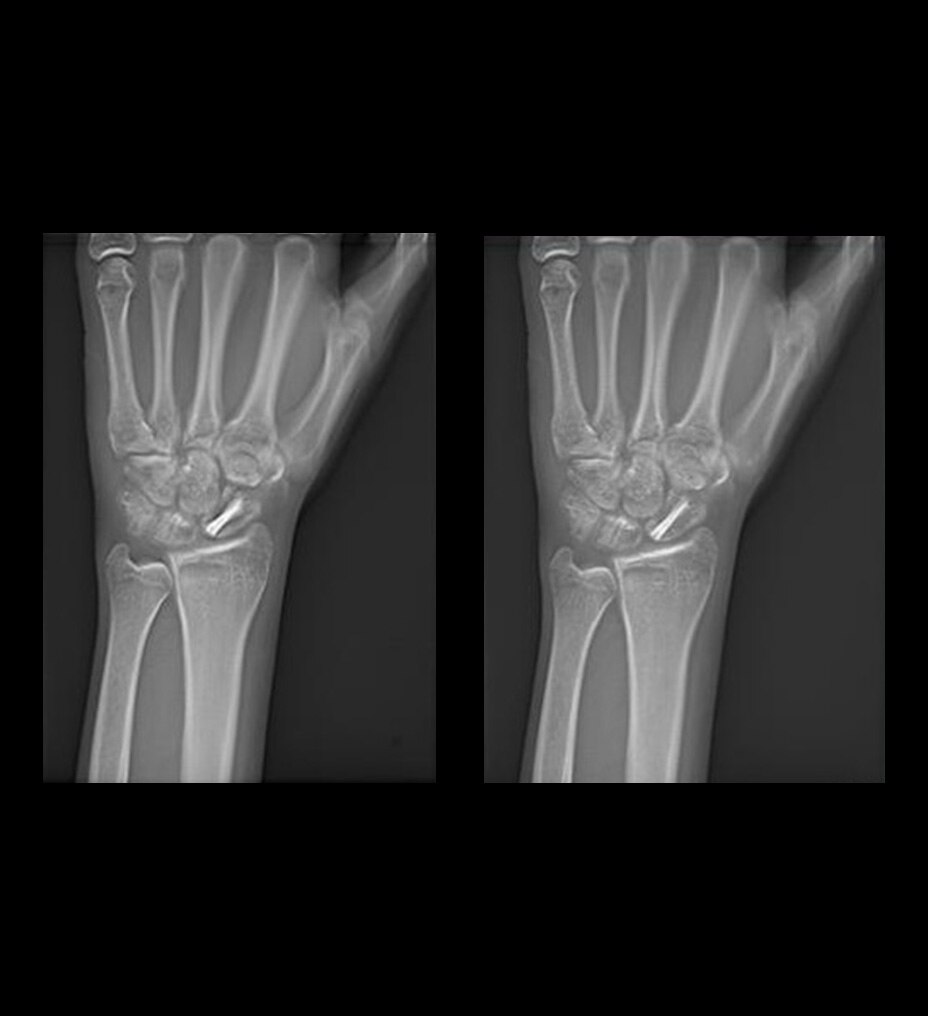

Calidad de imagen excepcional con AIR™ Recon DL

Las imágenes más claras le permitirán diagnosticar de forma más sencilla, y, gracias a nuestra tecnología de aprendizaje profundo líder en el sector, AIR™ Recon DL le ayudará a obtener imágenes excepcionales más rápido. Revoluciona la forma de visualizar las imágenes de RM, garantizando los resultados más nítidos en una amplia variedad de anatomías. Además, le permite tener más confianza en las imágenes adquiridas, con exámenes fáciles de interpretar y de alta calidad que también pueden reducir la fatiga ocular y mejorar la experiencia general de los informes.